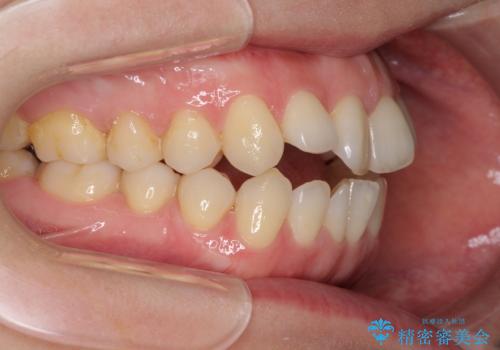

前歯の叢生とオープンバイト インビザラインでの矯正治療

- 前歯の開咬を気にして来院された患者様です。

開咬の治療は、前歯を閉じるように動かすとともに、上下臼歯を圧下(骨内にめり込ませる)させることで進めて行きます。

インビザラインは臼歯の圧下を効果的に行えるため、インビザラインを用いて矯正治療を行うこととしました。